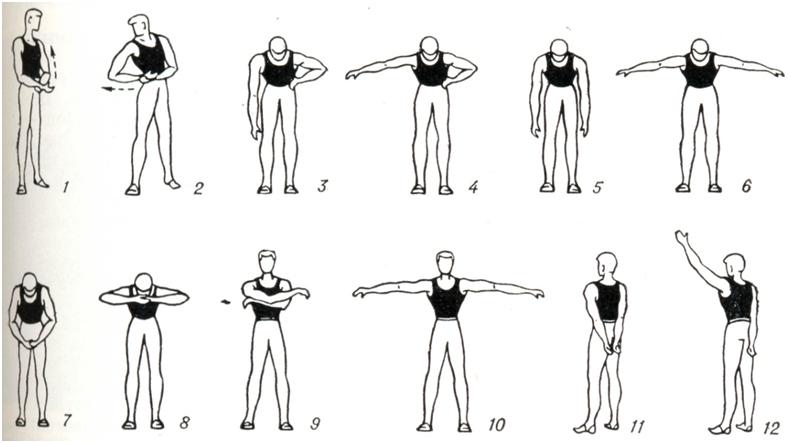

В терапии хронических артритов лечебная физкультура занимает важное место в клинической, в поликлинической и санаторно-курортной практике. При поражении суставов верхних конечностей упражнения выполняют преимущественно в положении сидя и стоя (рис. 11). При патологии суставов нижних конечностей в положении лежа, сидя и стоя тренируют опорную функцию ног (рис. 12). При заболеваниях позвоночника рекомендуют также и разгрузочные для позвоночника положения, например на четвереньках (рис. 13). Применяют упражнения активные: свободные, с усилием, с широким использованием различных снарядов, предметов и специальных приспособлений (особенно для восстановления функции кисти, в целях бытовой и трудовой реабилитации и так далее). Дополнительно используют упражнения на механотерапевтических аппаратах. Больным рекомендуется выполнение самостоятельных занятий с повторением заданий в течение дня до 4—6 раз продолжительностью по 5 — 7 мин. в целях тренировки пораженных суставов. Кроме того, полезна утренняя гигиеническая гимнастика, прогулки. Целесообразно лечебную физкультуру проводить в сочетании с массажем, бальнео- и грязелечением.

Рис. 12. | ||